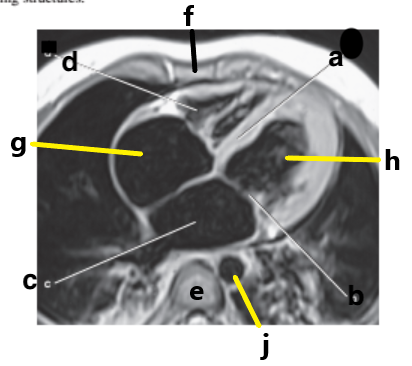

Which letter is the Pulmonary trunk ?

d

Which letter is the Descending aorta ?

f

Which letter is the superior vena cava ?

Which letter is the ascending aorta ?

What is letter a ?

Ascending aorta

Aortic Arch

What is letter d ?

Right ventricle

Pulmonary trunk